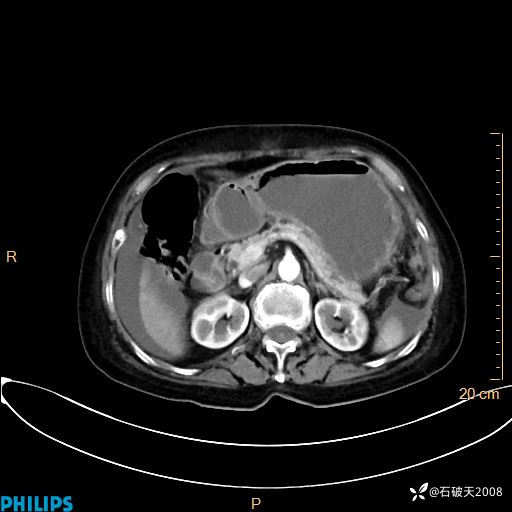

动脉期